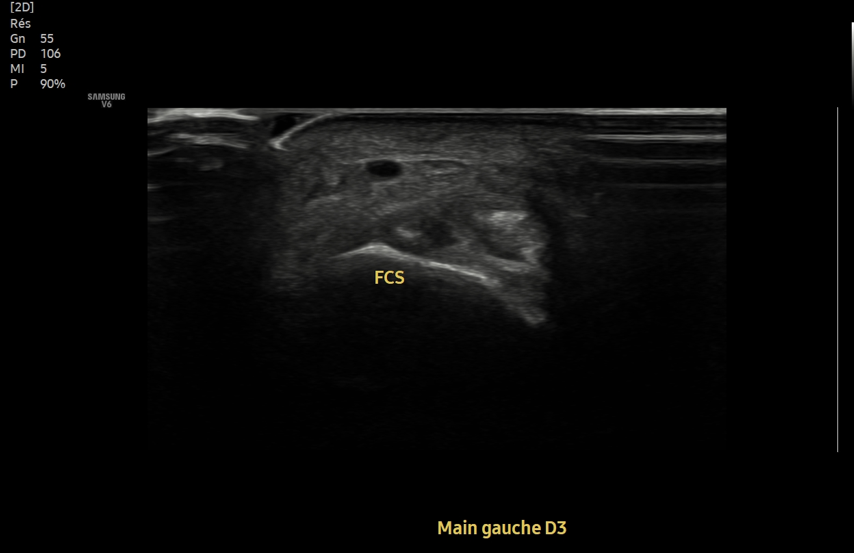

Consent ✅

F 60s

Years of diffuse R gluteal, hip & thigh pain, constant, stairs & sitting aggravates

Seen by orthopaedics to evaluate hip & knee (previous patellectomy this side) - referred to me as unable to identify pain driver & MRI scans 'normal'

MRI pelvis - hip joints & lateral soft tissues are fine

Clear suspect for her pain though, even on first glance - what do you see?